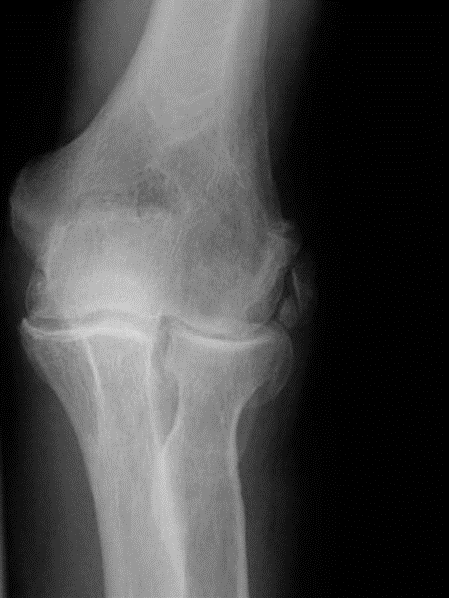

Elbow structured oral examination question 3 EXAMINER : What do you see in this radiograph of a 67- year-old …